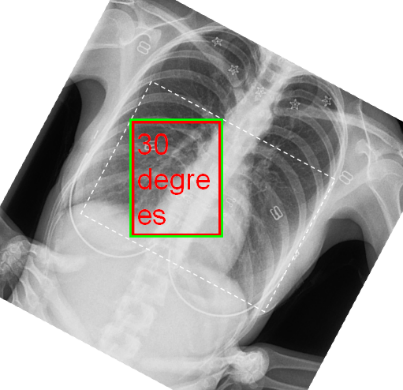

However, if the rectangle defining the area is allowed to rotate without rotation of the text, then the text and its container are mis-matched shapes, and some ambiguity arises. In these images, the green rectangle is the largest "straight" rectangle fitting within the rotated rectangle:

The above is the default behaviour of versions until now, inherited from V6, and whilst it makes some sense for the multiples of 90°, it makes no sense for other angles, and will therefore be dropped from now on. In its place will be a new "NoRotation" mode, which acts in an analogous but reversed manner to the simple rotation of an image without being image tied - i.e. the text will retain the same size and shape as if the image were NOT rotated. Like the simple rotation, this requires definition and use of a "rotation point", and the same RotationPoint and RotationCentre(X/Y) properties but in this case the definition will be in image pixel coordinates.